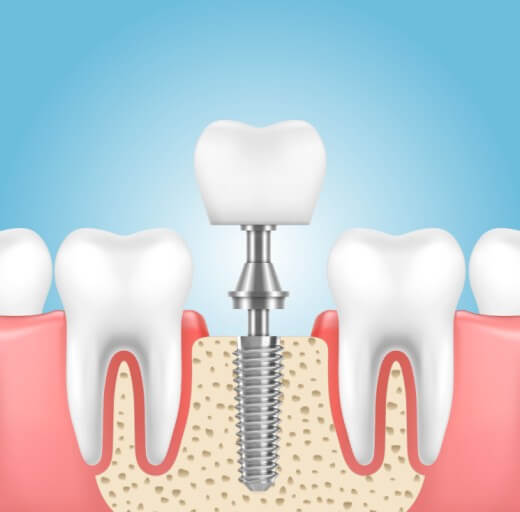

임플란트란?

임플란트는 쉽게 말씀드리면 치아를 제거한 부위에 인공적으로 만든 치아를 즉, 임플란트를 식립 하는 시술입니다.